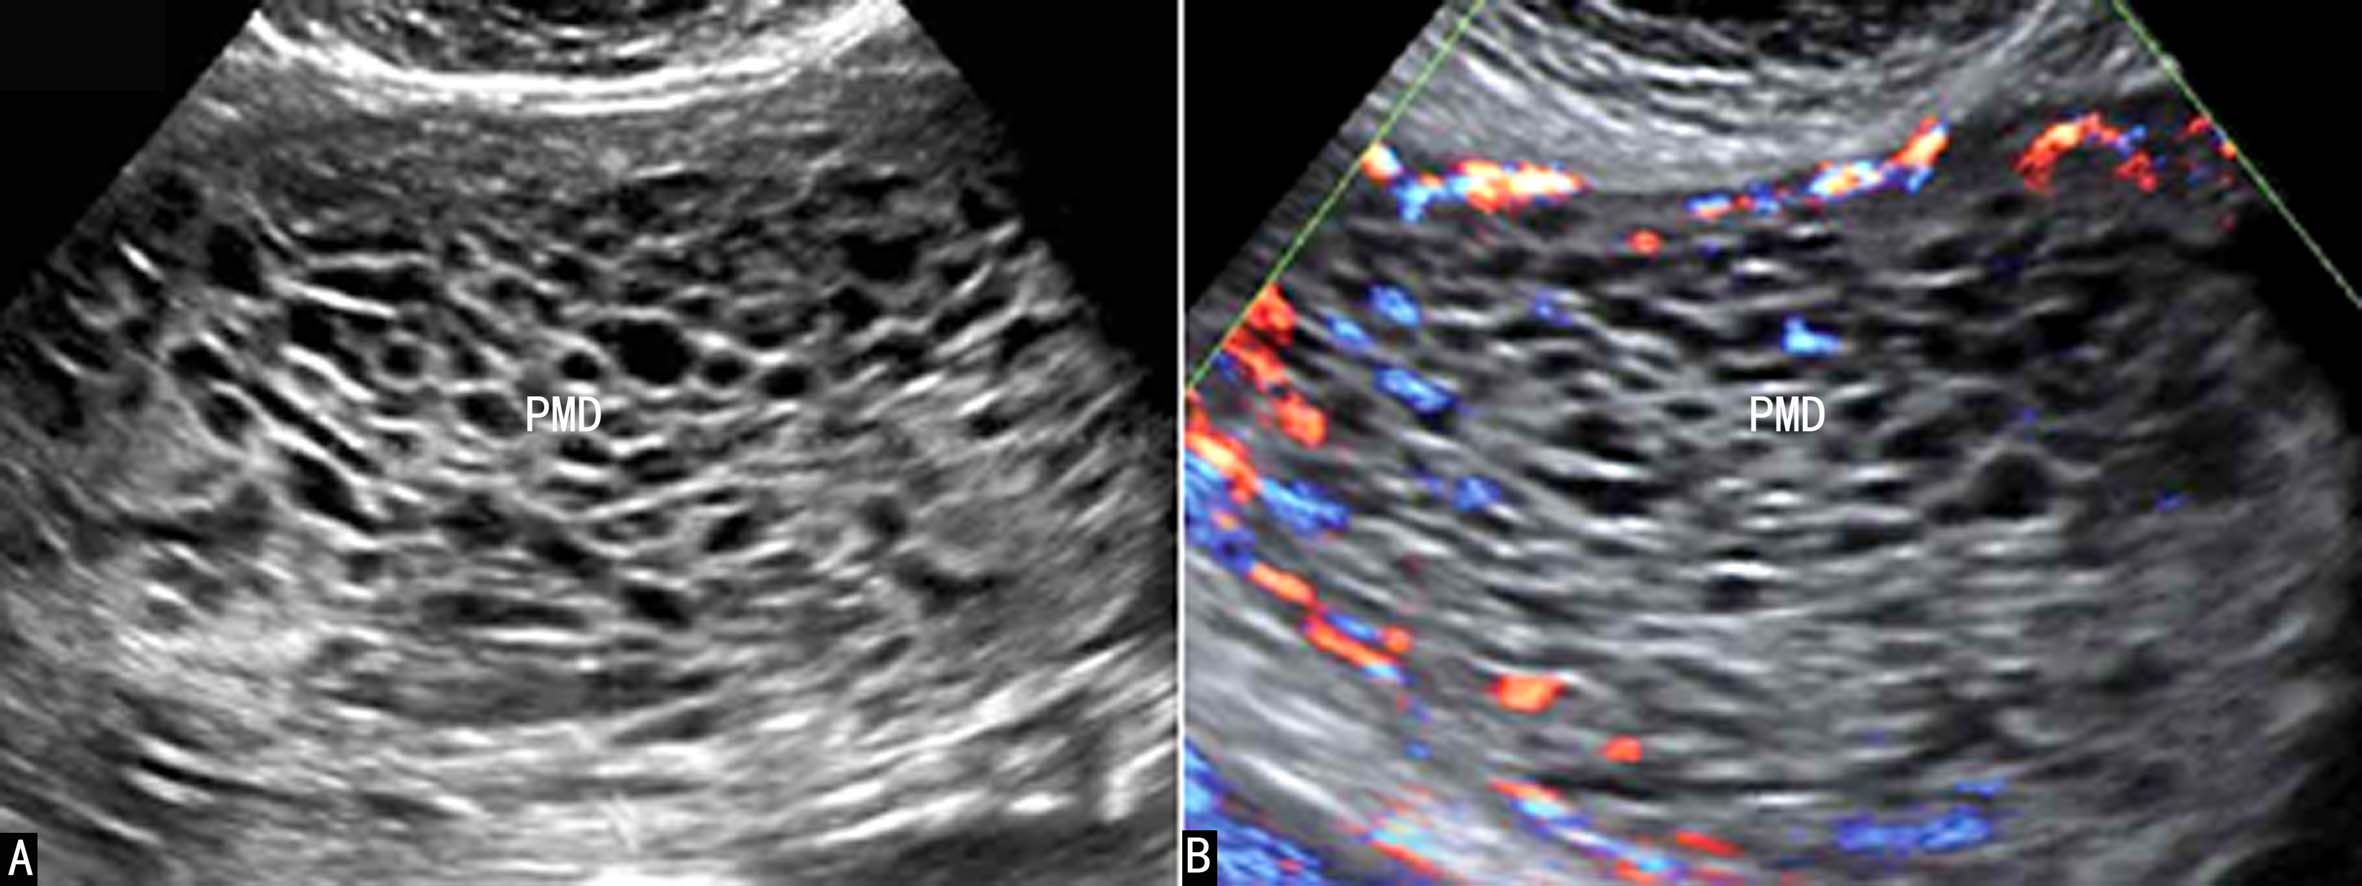

2D-US最早有报道在11孕周发现胎盘异常回声(图4A),显示为胎盘较正常增大,部分区域可见蜂窝状无回声(图4B),CDFI检查显示血流增多,声像图表现类似葡萄胎,胎儿发育未受到影响,孕妇血hCG在正常范围内,而AFP则显示增高。此后PMD声像图显示逐渐明显。2D-US显示胎盘增厚、增大,内部显示蜂窝状无回声,可以是部分性或占据整个胎盘(图4、图5),需要注意与绒毛血管瘤、胎盘出血、胎盘梗死以及不全流产水泡样等变进行鉴别。超声多普勒血流显像检查对PMD与葡萄胎、胎盘出血、胎盘梗死的鉴别很有价值。葡萄胎时病变内部常显示丰富的血流,PW检查可以记录到高速、低阻力血流频谱;胎盘血管瘤多显示为胎盘胎儿面凸向羊膜腔的局限性回声,边缘清楚,内部回声强度不等,分布不均匀,内部如果有血流显示,则其血流性质与脐带血流一致;PMD也可以显示为局部的瘤样回声,但内部血流较少或没有明显血流显示,也不能记录到类似脐带的低阻力血流频谱。

图5胎盘间质发育不良